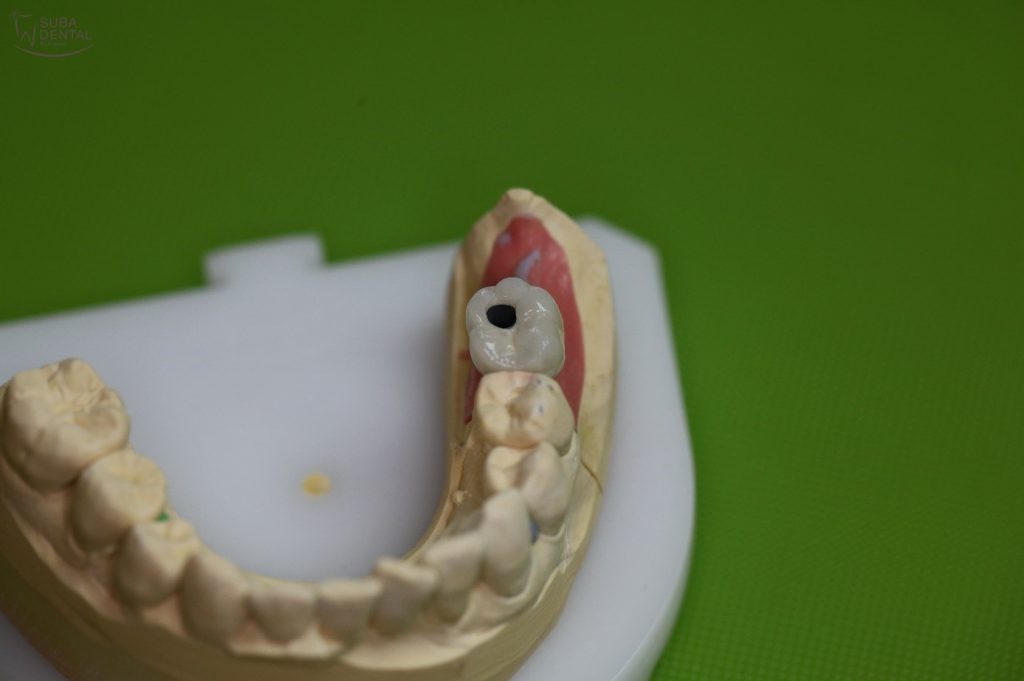

Csavarozható fémkerámia korona a bal alsó hatos helyére beültetett DIO implantátumra

Csavarozható fémkerámia korona a mestermintáról levéve a rögzítést szolgáló átmenő csavarral